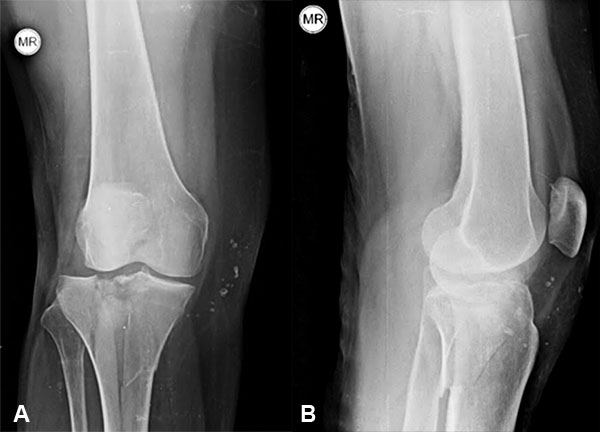

Nuestro seguimiento osciló entre 6 meses y 24 meses, sin que observáramos cambios radiográficos.

Radiológicamente obtuvimos 7 resultados excelentes y 1 bueno. En todos los casos no observamos desplazamientos secundarios de la fractura y obtuvimos la consolidación definitiva.

La reducción anatómica ayuda a evitar la pérdida de la movilidad, retrasa los cambios degenerativos articulares y es el mayor indicador pronóstico de estas lesiones. Blokker y cols. y Waddell y cols.,14,15 enfatizaron en la calidad de la reducción como el factor más importante.

Un estudio comparativo realizado por Fowble y cols.,16 entre el tratamiento artroscópico y las técnicas tradicionales a cielo abierto, concluyó que sólo en un 55% de este último grupo se llegó a la reducción anatómica. Los resultados obtenidos en nuestra serie avalan esos conceptos.